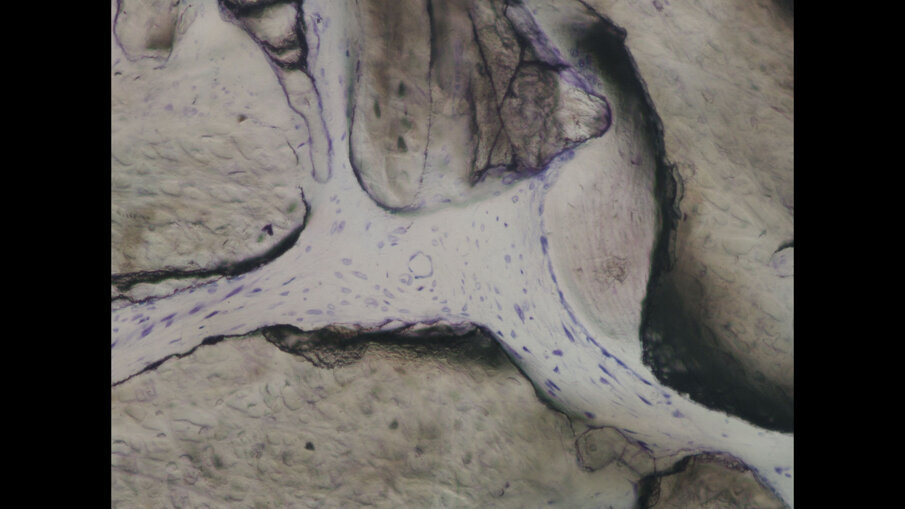

A distanza di 3 mesi, si procede alla seconda fase implantare abbinata a una vestiboloplastica, col fine di ripristinare la profondità del fornice vestibolare ed un’idonea anatomia dei tessuti molli perimplantari (Figg. 14, 15). Le biopsie del tessuto osseo prelevate in fase di inserimento implantare sono state processate con tecnica standard, non decalcificata, e colorate con blu di toluidina e pironina gialla.

A 9 mesi dalla chirurgia ricostruttiva, si riscontra una buona stabilità dei tessuti duri e molli perimplantari (Figg. 16, 17). All’esame istologico descrittivo (Fig. 18) si riscontrano granuli residui del biomateriale utilizzato per la rigenerazione, a stretto contatto col tessuto osso neoformato. Cellule simil-osteoblastiche sembrano allineate lungo il fronte di rigenerazione ossea. Gli spazi midollari appaiono ricchi di vasi e privi di infiltrato infiammatorio.

Fig. 18 - Immagine ad alto ingrandimento (400x) di una sezione istologica non decalcificata e colorata con blu di toluidina e pironina gialla.